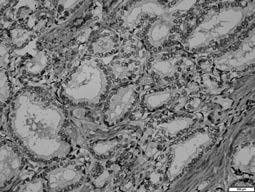

Inmunohistoquímica negativa para receptores hormonales. 40 x

Figura 2: Inmunohistoquímica negativa para receptores hormonales. 40 x

Fuente: los autores.

Se incluyen estudios de patología de diez hombres, diagnosticados e intervenidos por cáncer papilar de tiroides variedad clásica. Siete de estos pacientes fueron sometidos a tiroidectomía total y tres requirieron adicionalmente disección de cuello por compromiso ganglionar a ese nivel. El rango de edad fluctuó entre 32 y 70 años, con un promedio de 46 años. Todas las biopsias de estos pacientes, evaluadas mediante técnicas de inmunohistoquímica, fueron negativas para estrógenos y progestágenos (figuras 1 y 2).